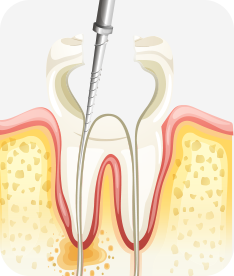

신경치료

자연치아를 살라기 위한 가장 기본적이고 중요한 치료입니다

치아 외상이나 충격, 깊은 충치 등의 이유로 치아 내부의 신경과 세포 조직에 염증이 생겼을 경우, 이 를 제거하고 소독하여 생체친화적인 특수 재료로 신경관을 충전해 치아의 기능을 유지할 수 있는 중요한 치료입니다.

사람마다 치아의 모양이나 치아 내부 신경관의 모양도 다 다릅니다.

3차원적인 신경관 내부를 치아 밖에서 도달하여 뿌리 끝까지 정밀하고 정확하게 치료해야 하는 신경치료는 가장 기본적인 자연치아 살리기 치료이자 고난이도 치료입니다.

치아신경 염증

충치가 심해져 치아 뿌리까지 신경 염증이 발생함

신경소독

충치를 제거하고, 치아 뿌리 끝까지 신경관 내부의 염증 물질들을 제거하고 소독함

신경치료 완료

소독된 신경관을 생체친화적인 재료로 충전한 후 보철치료를 함